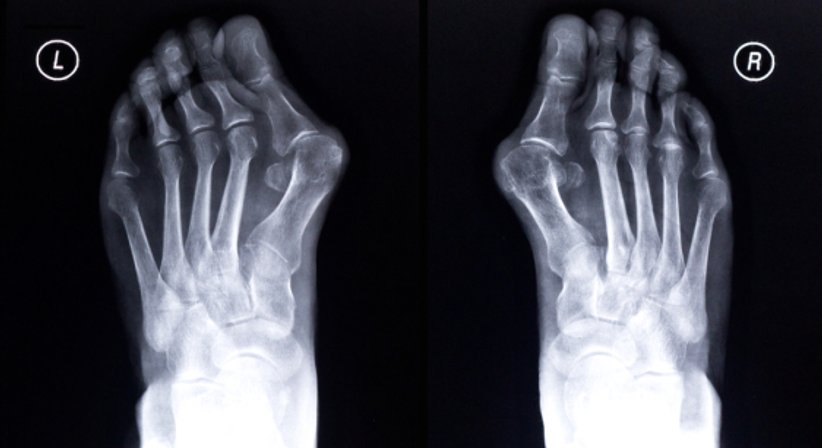

Der Hallux valgus ist eine fortschreitende Erkrankung des Vorfußes und die häufigste Fehlstellung der Zehen. Beim Hallux valgus ist die Großzehe nach außen in Richtung der kleineren Zehen abgeknickt, wodurch diese von ihrer Position verdrängt werden.

Der hervorstehende und für die Fehlstellung charakteristische Ballen drückt häufig gegen den Schuh, was mit der Zeit zu Schmerzen führt und die Gelenkkapsel anschwellen lässt. Nimmt die Schwellung zu, verstärkt sich wiederum die Reibung des Ballens am Schuh. Mit fortschreitendem Verlauf verändert sich auch die Gewichtsverlagerung des Fußes, nämlich weg von der Großzehe und hin zu den kleineren Zehen, was zu deren Überlastung und in weiterer Folge zu Schmerzen im Bereich vom Mittelfuß führen kann. Weitere mögliche Spätfolgen sind ein verändertes Gangbild, Gangunsicherheit, weitere Fehlstellungen (z.B. Krallen- und Hammerzehen), Arthrose am Großzehengrundgelenk und andere.

Die Fehlstellung selbst lässt sich allerdings nur im Rahmen einer Operation korrigieren, mit einer konservativen Behandlung kann ein Hallux valgus nicht "zurückgestellt" werden. Es stehen zahlreiche Operationstechniken zur Verfügung, viele davon unterscheiden sich teils nur in Details voneinander. Welche Operationstechnik im Einzelfall am besten geeignet ist hängt vom Schweregrad der Fehlstellung, von möglichen Begleiterkrankungen und anderen Fehlstellungen des Fußes sowie von anderen Faktoren ab und wird nach Vorliegen der Diagnose im Detail besprochen.